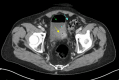

Figure 2. Axial computed tomography of the abdomen and pelvis with intravenous and oral contrast (Gastrografin).

Gas locules (yellow arrow) and anti-dependent gas (green arrow) within the bladder and adjacent sigmoid diverticulitis (blue arrow) consistent with colovesical fistula.